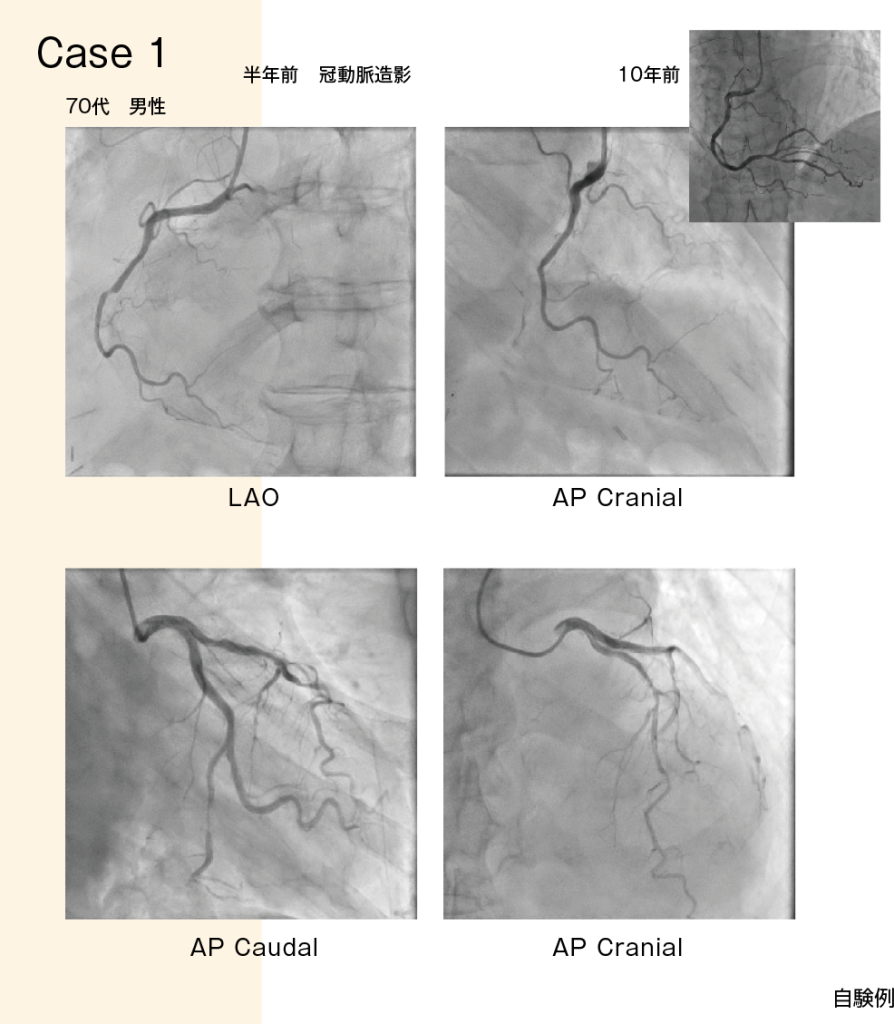

- ■症例 70代男性 労作性狭心症

約30年前に左前下行枝(LAD)にベアメタルステント留置

長らく経過良好であり、10年前の心筋SPECTでは集積低下を認めなかった。薬物治療を継続していたが、心エコー図で左室下壁の壁運動異常を認めたため、半年前に心筋SPECTの再検査を実施した。負荷時像、安静時像共に壁運動異常の領域に一致して高度集積低下を認め、左室下壁の心筋障害が示唆された。また、左室前壁中隔にも軽度の集積低下がみられた(図1)。

【図1】

こうした新たな所見を踏まえ、10年ぶりに冠動脈造影(CAG : coronary angiography)を施行した。すると、右冠動脈(RCA)は右室枝(RV branch)の分岐部で完全閉塞しており、順行性の血流はほとんど認められなかった(図2上)。左冠動脈(LCA)に関しては、左回旋枝(LCx)末梢に狭窄があり、左前下行枝(LAD)にもびまん性に狭窄を認めた(図2下)。

【図2】